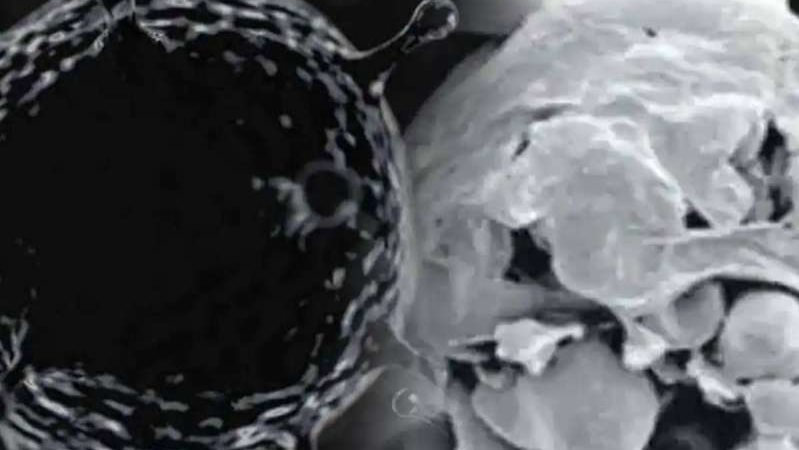

بعد انتشار الفطر الأسود الذي تسبب في إصابة الكثير من مصابين كورونا في الهند تم العثور على حالات الجديدة من الفطر الأبيض وهذه العدوى أكثر خطورة من الفطر الأسود

وتكون عدوي أكثر خطورة من عدوى الفطريات السوداء لأنها تصيب الرئتين وكذلك أجزاء أخرى من الجسم بما في ذلك الأظافر والجلد والمعدة والكلى والدماغ والأجزاء الخاصة والفم.